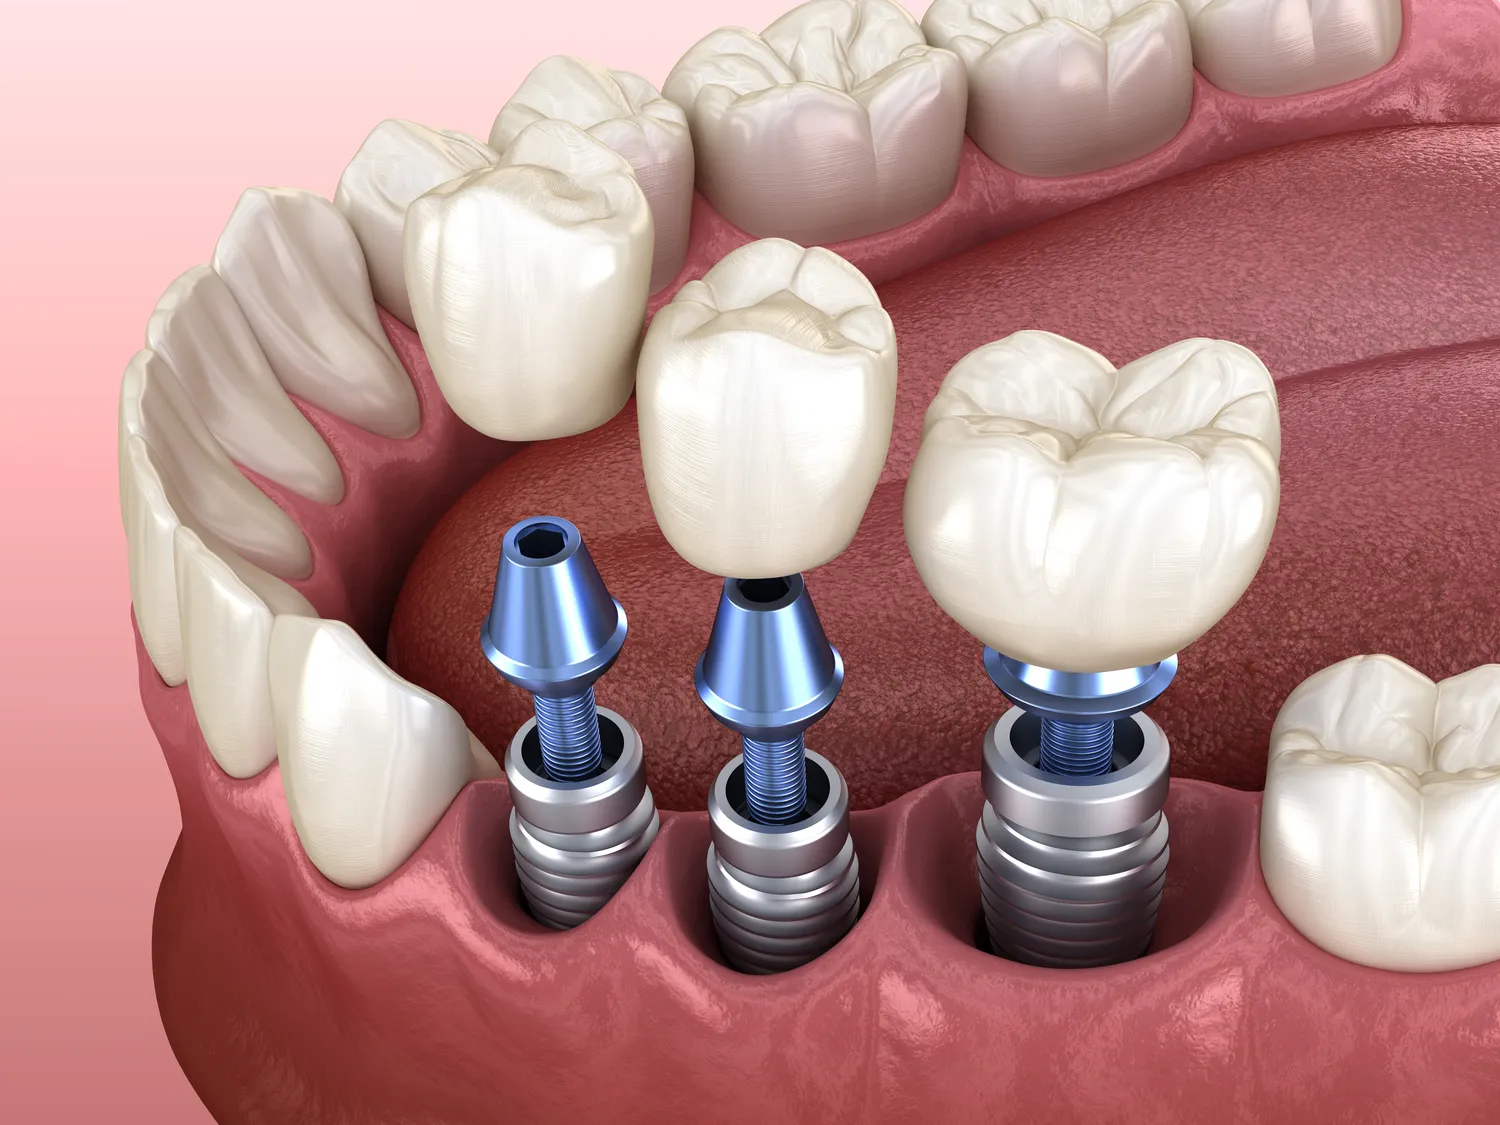

Implanty zębów to coraz popularniejsza forma leczenia stomatologicznego, która pozwala na przywrócenie estetyki oraz funkcji żucia. Wiele osób zastanawia się, czy wydatki związane z ich wszczepieniem mogą być odliczone od podatku dochodowego. W Polsce istnieje możliwość odliczenia niektórych wydatków medycznych, jednak zasady te są dość skomplikowane i wymagają dokładnego zapoznania się z przepisami prawa. Zgodnie z obowiązującymi regulacjami, aby móc skorzystać z ulgi podatkowej, wydatki muszą być potwierdzone odpowiednimi dokumentami, takimi jak faktury czy rachunki. Ważne jest również, aby koszty były związane z leczeniem uzębienia i nie przekraczały określonych limitów. Warto zwrócić uwagę na to, że nie wszystkie zabiegi stomatologiczne kwalifikują się do odliczenia, a implanty mogą być traktowane różnie w zależności od konkretnej sytuacji pacjenta.

Implanty zębów są często klasyfikowane jako wydatki medyczne, co oznacza, że mogą być brane pod uwagę przy obliczaniu ulg podatkowych. Jednakże nie wszystkie procedury stomatologiczne są traktowane w ten sam sposób i istotne jest, aby dobrze rozumieć różnice między nimi. W przypadku implantów kluczowe jest to, że są one przeznaczone do odbudowy utraconego uzębienia i mają na celu poprawę jakości życia pacjenta poprzez przywrócenie funkcji żucia oraz estetyki uśmiechu. W wielu krajach wydatki na implanty mogą być odliczane jako część kosztów leczenia uzębienia, ale zasady te mogą różnić się w zależności od lokalnych przepisów prawnych. W Polsce konieczne jest spełnienie określonych warunków oraz posiadanie odpowiedniej dokumentacji potwierdzającej celowość i zasadność poniesionych wydatków.

W ostatnich latach implantologia stomatologiczna znacznie się rozwinęła, a nowe technologie wprowadziły wiele innowacji, które poprawiają efektywność oraz komfort leczenia. Jednym z najważniejszych osiągnięć jest zastosowanie technologii cyfrowej, która umożliwia precyzyjne planowanie zabiegów oraz tworzenie indywidualnych modeli implantów. Dzięki skanowaniu 3D można dokładnie ocenić stan kości pacjenta i zaplanować wszczepienie implantu w sposób minimalizujący ryzyko powikłań. Kolejną nowością są implanty o zwiększonej biokompatybilności, które lepiej integrują się z tkankami kostnymi, co przyspiesza proces gojenia. Warto również wspomnieć o technice wszczepiania implantów w jednym dniu, która pozwala na natychmiastowe umieszczenie korony na implancie, co znacząco skraca czas leczenia. Takie innowacje sprawiają, że implanty stają się coraz bardziej dostępne i komfortowe dla pacjentów, a ich skuteczność rośnie.